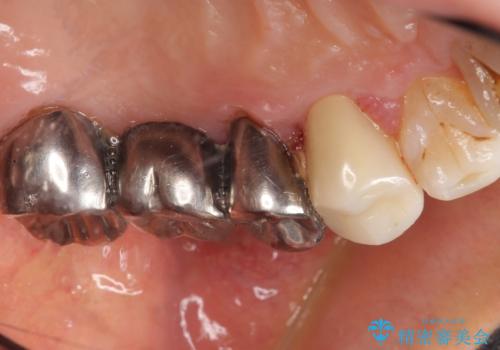

保存不可能な歯(左上4)を抜去後、ブリッジによる補綴治療を行いました。

- ¥760,000 (根管治療×2本、土台×2本、仮歯×5本、クラウン×5本)費用は治療当時の料金となります

自然な仕上がりと咬み心地に喜んで下さいました。

歯茎の腫れも治り、ご満足頂けました。

クラウンの種類:メタルボンドクラウン エコノミー